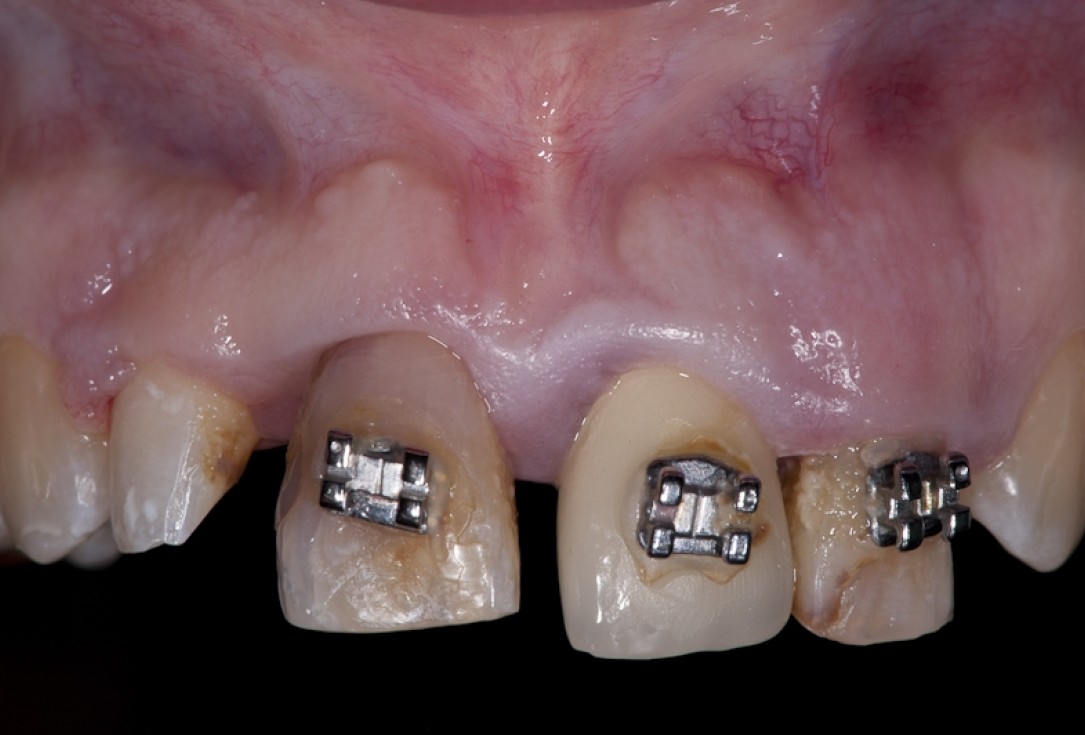

Left maxillary incisior with failing endodontic treatment despite apicoectomy which was done 15 years prior